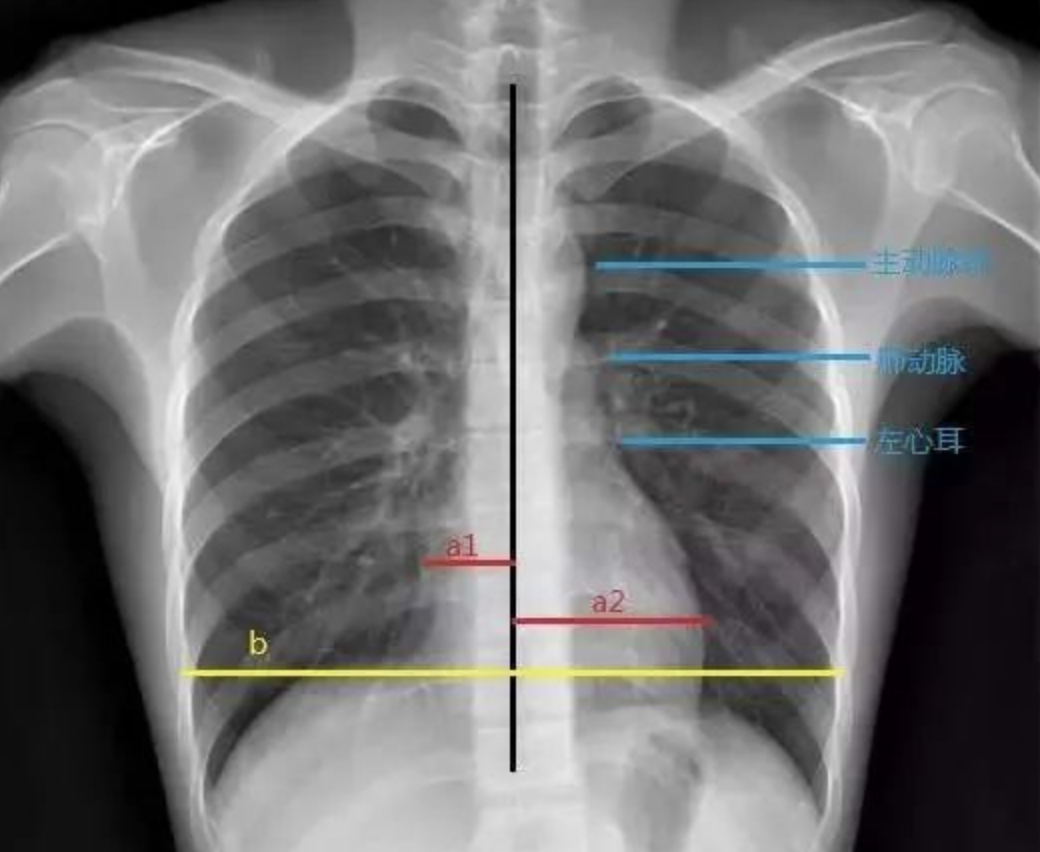

图2-22二尖瓣型心脏(梨型心)2.

瓣膜病杂音;梨形/靴形/普大 心 心脏瓣膜病的特征性/典型杂音; 梨形心

看图(扩张型心肌病,全心衰-心肌无力了)要么是心脏本身增大(心包积液